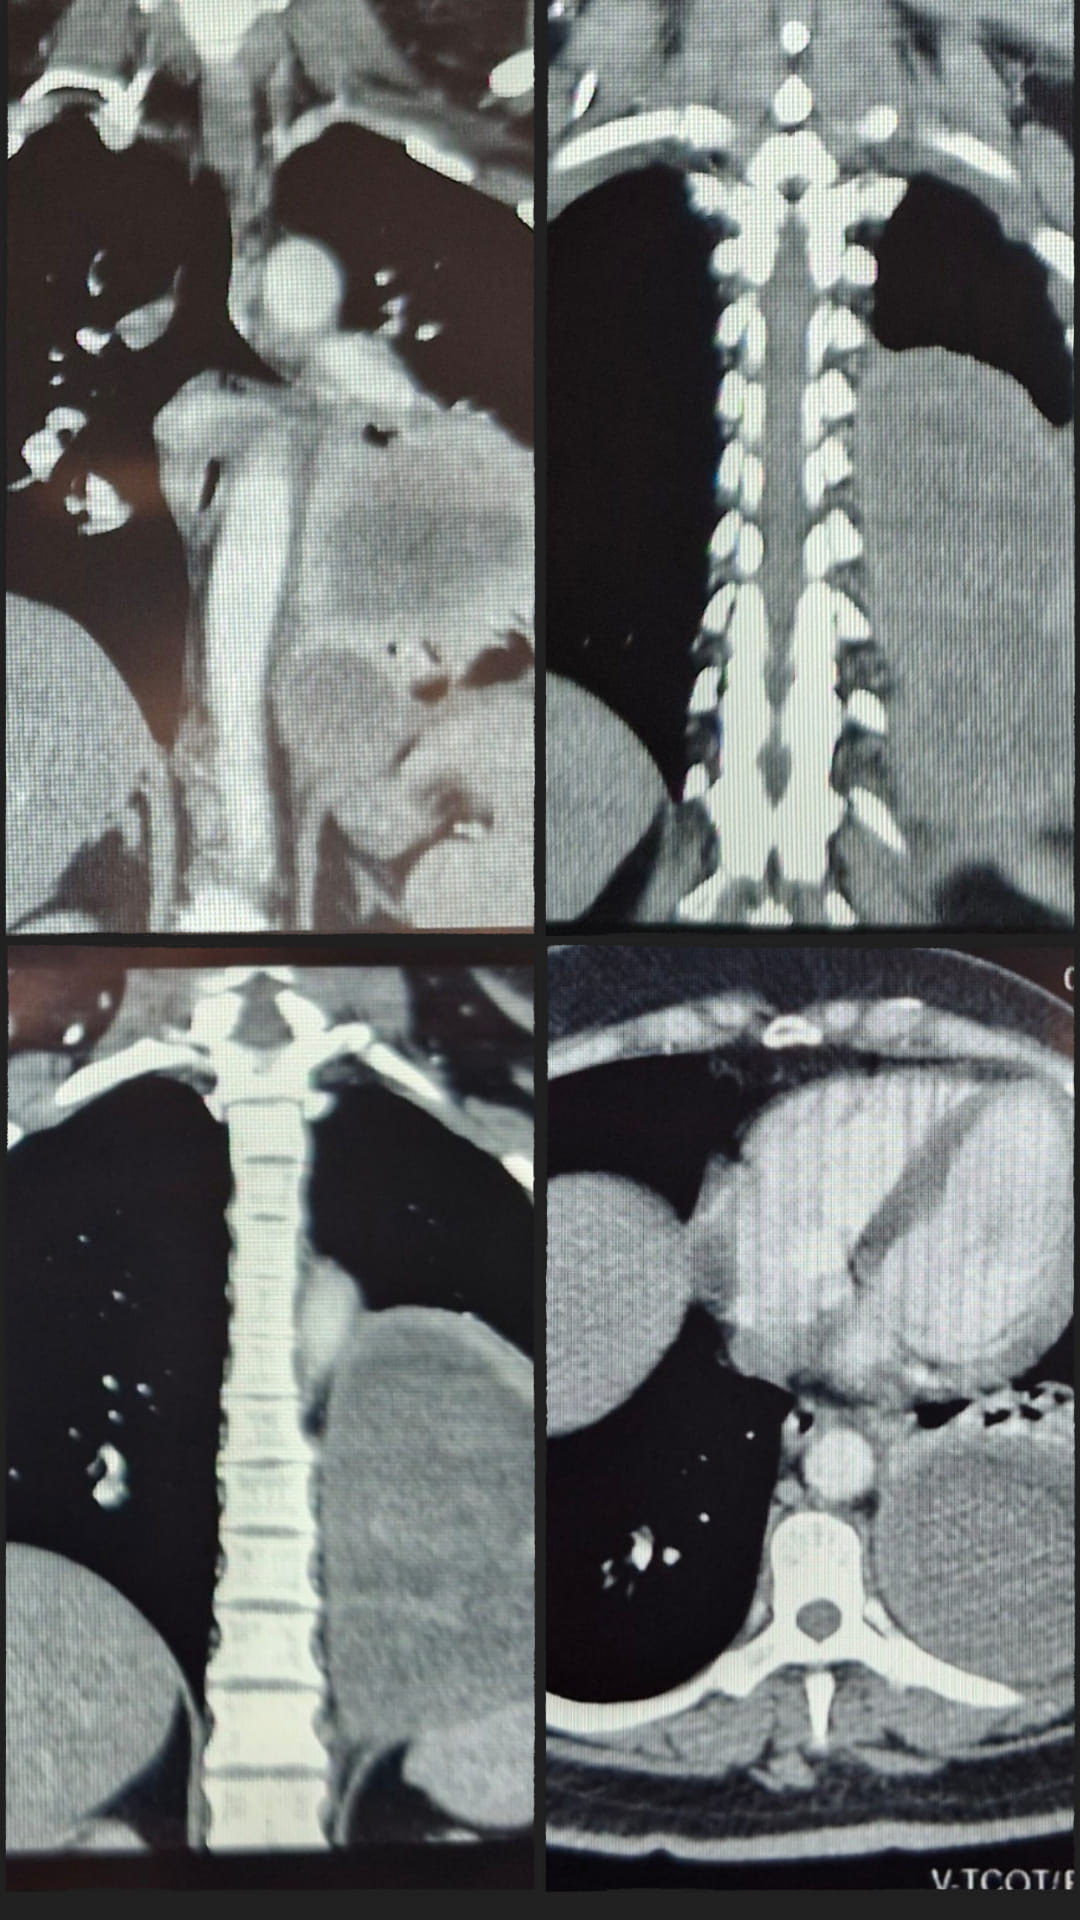

User Image